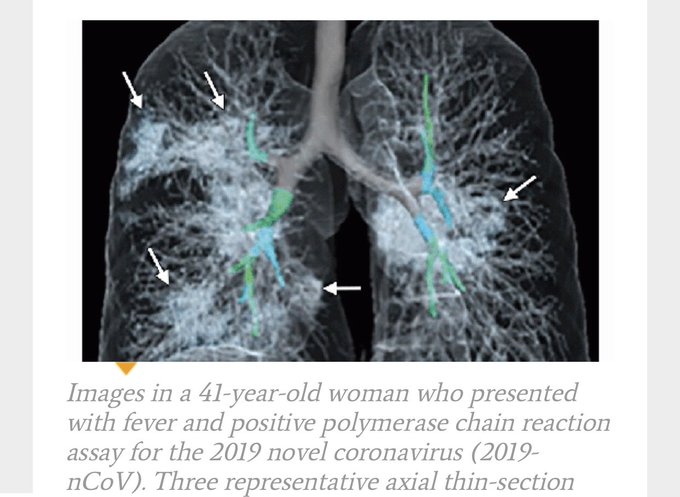

De beelden van de foto’s wisselen, maar in het algemeen ziet men in verschillende longgebieden ontsteking, zoals hier: pic.twitter.com/PeGH8caDbI

— Sander de Hosson (@shossontwits) March 1, 2020

De witte gebieden met pijltjes zijn de gebieden van de longontsteking, die op deze foto zwart horen te zijn. U ziet uiteraard ook de bronchieën en de bloedvaten.